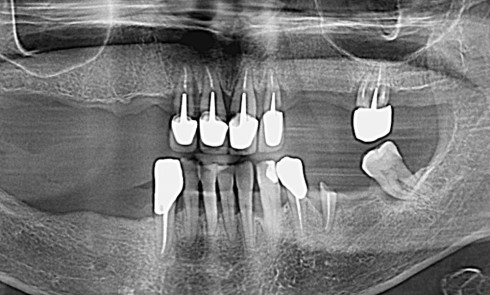

Contexte clinique et objectifs Une patiente partiellement édentée mandibulaire se présente avec les dents 33, 35, 36 et 43 compromises (alvéolyse...